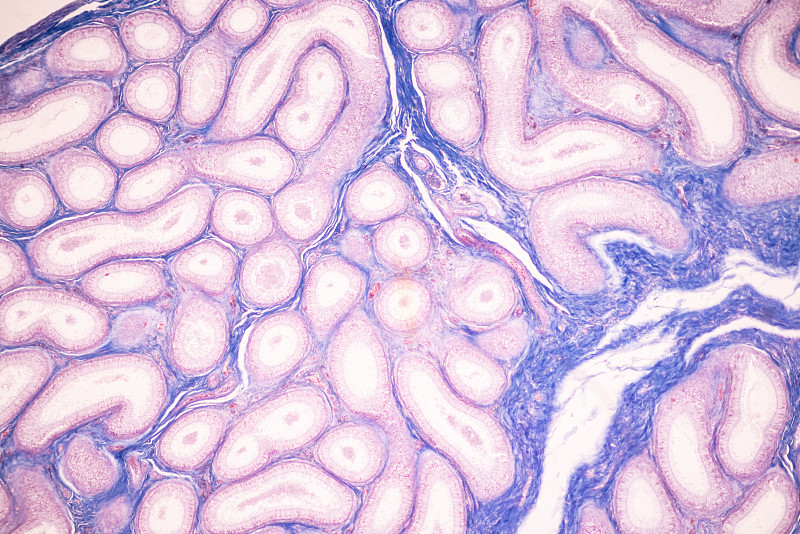

显微镜下的人类细胞详情

JPG